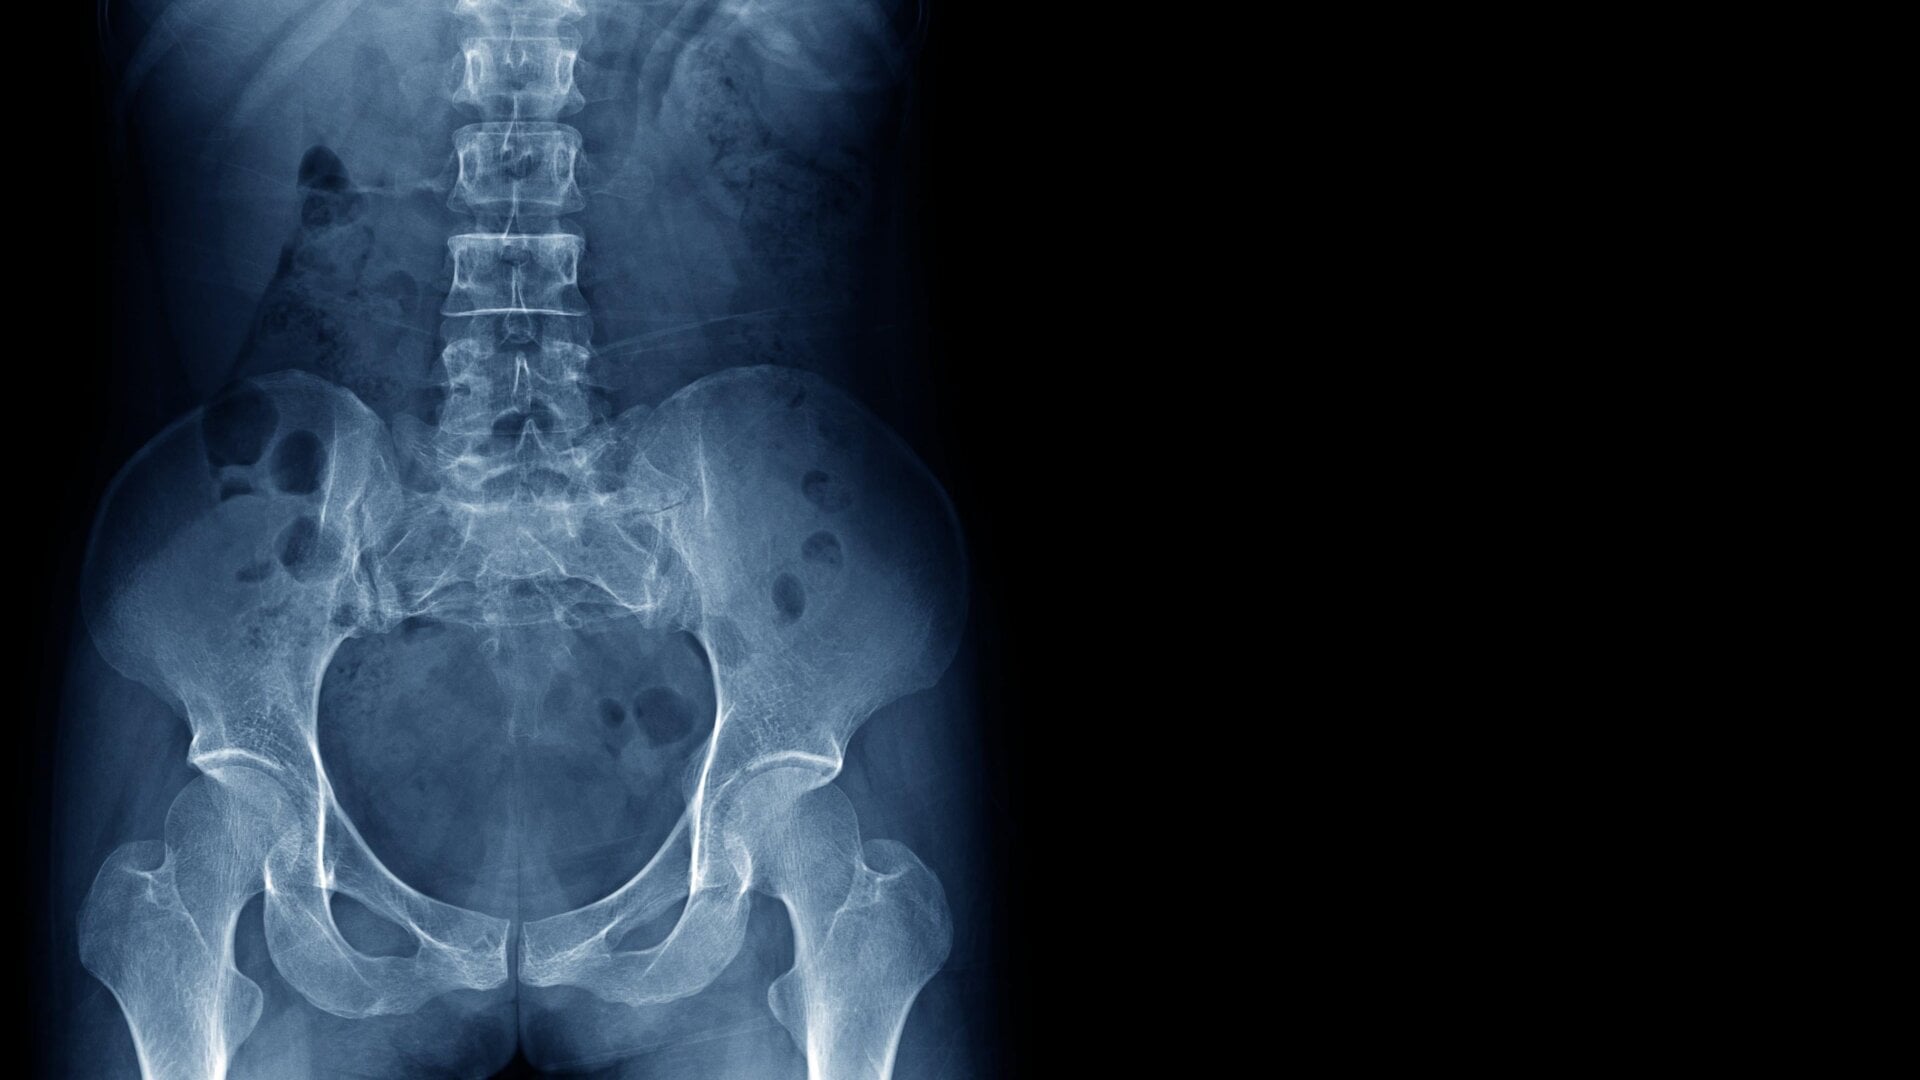

Fun as being nearly weightless might seem, the microgravity environment of space can have profoundly negative effects on our bodies if we stay up there too long. Our bones in particular actually depend on regular mechanical stress to stay healthy, much of which comes from fighting against Earth’s gravity. Without this stress, the body’s production of bone-building cells (called osteoblasts) starts to slow down. Coupled with the constant wearing down of our bones, this leads to progressive bone loss, which can then raise the risk of fractures during the mission and possibly even later on in life. Astronauts can lose up to 1% of their bone mass for every month they spend in space, while recovery back on Earth can take years following a long trip.